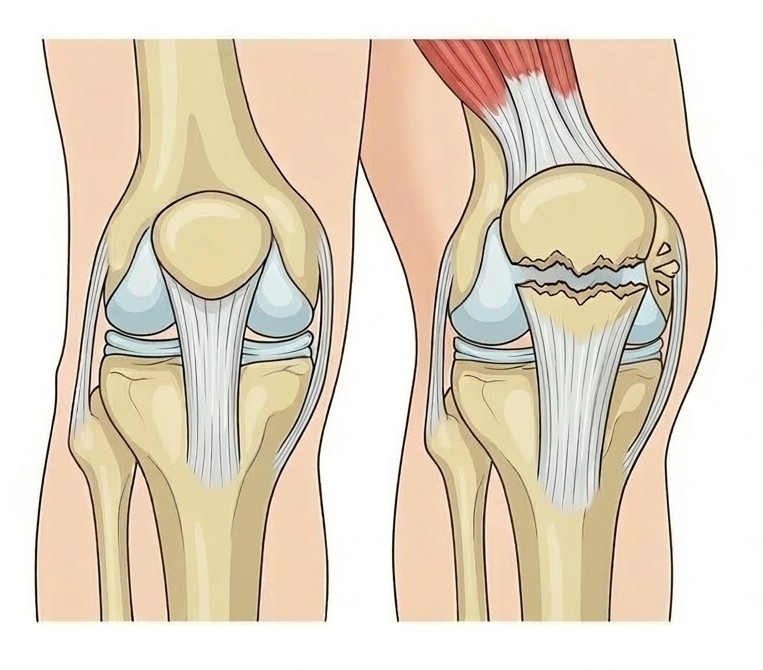

膝蓋骨(しつがいこつ)は、いわゆる「お皿」と呼ばれる膝の前面にある骨で、太ももの筋肉(大腿四頭筋)の力を効率よくすねに伝える重要な役割を担っています。この骨が割れてしまうケガが膝蓋骨骨折です。

膝蓋骨は膝を伸ばす機構の一部であるため、骨折により脚を自力で持ち上げられなくなることが特徴的です。